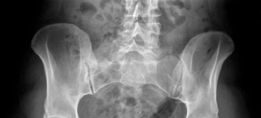

A 29-year-old man is brought into the emergency department after falling off his motorcycle in wet weather. H…